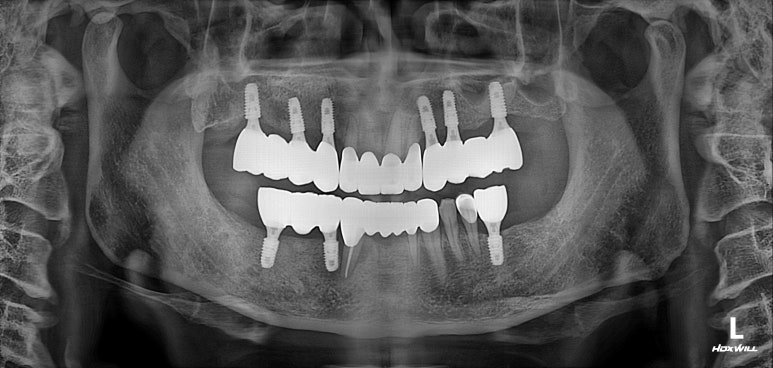

전체 임플란트 완성!!

어느 정도 적응이 되시면, 그 교합을 반영하여 최종 임플란트 크라운을 제작하게 되고 위와 같이 깔끔하게 완성되게 됩니다...

Before & After

정면부터 비교도 안되게 좋아지신 것을 보실 수 있을겁니다.

위 앞니는 지르코니아 크라운으로, 아래 앞니는 지르코니아 브릿지로 새로 제작하여 적절한 overjet과 overbite를 형성하였고 상당히 자연스러운 외형을 갖춘 것을 보실 수 있을거에요.

또한 앞니를 크라운으로 제작하면서 치아의 색상도 보다 톤업해드렸고, 치아 배열도 가지런하게 그리고 치아 사이 공간도 모두 닫아드려 정말 한결 젊어졌다는 느낌이 듭니다.

임플란트를 엄청 많이 심지 않았지만, 적절한 개수를 식립해냄으로써 성인 남성도 식사가 가능할 정도의 임플란트 크라운을 제작해드릴 수 있었습니다.

앞니와 어금니를 한 번에 다 같이 만들었던 만큼, 크라운 색상의 조화가 기가막혀 진짜 내 이같아 보이네요..!!

이루 말할 것 없이 깔끔하게 정리된 교합면 사진입니다.

사실 각 어금니마다 1개씩 임플란트가 더 식립되는 것이 28개의 치아를 재건하는데 필수적이나, 남성임에도 불구하고 턱이 아주 크진 않으셨기에 24개의 크라운만으로도 충분히 만족스러운 결과를 얻을 수 있었습니다.!!

다시봐도 지르코니아 크라운의 색상은 너무나 자연스러운 것 같아요... 상당히 완성도 있게 마무리 되었던 케이스였습니다. 개원 초기부터 믿고 잘 따라와주심에 감사드립니다 :)